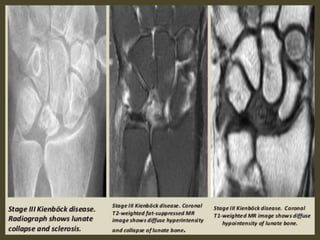

Keinbock,s Disease.